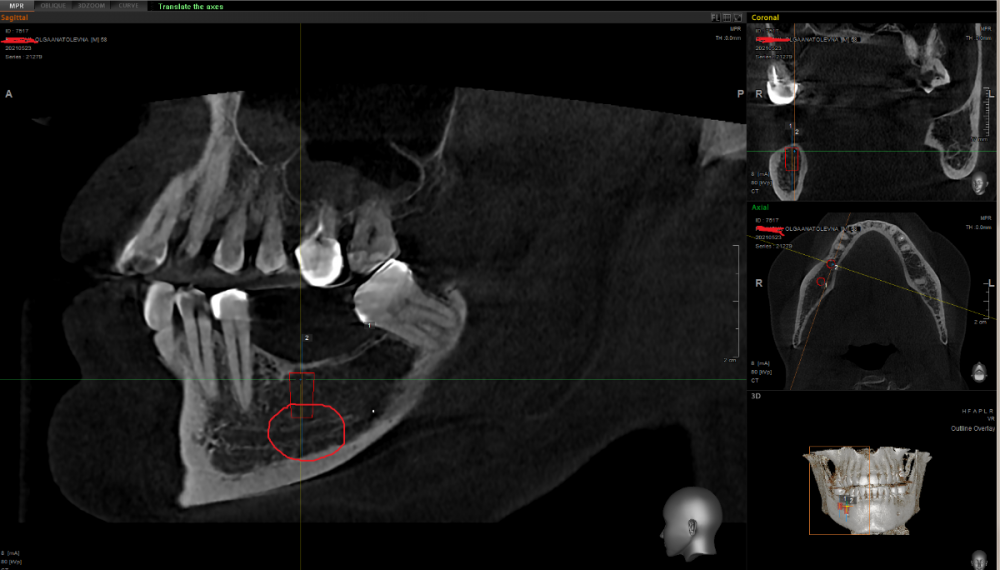

It'sGeorgy Опубликовано 17 сентября, 2021 Поделиться Опубликовано 17 сентября, 2021 (изменено) Добрый день! У пациентки тонкий биотип. Десна над планируемым 4.6 имплантатом была не более, чем в 1мм в высоту. Первым этапом уже удалил 4.8, положил с бугра небольшой сст(большой брать неоткуда) в область 4.6 и ушил. Надеюсь, получу хотя бы 1.5мм на этапе имплантации. С кератинизацией больших проблем нет. Планирую короткие(6мм) имплантаты, ибо если ставить 4.6 длинной 8мм возникает вот такая инт близость с каналом. На такой риск идти не готов: Скрытый текст Идем дальше: 4.6, наверняка, придется немного затопить, ибо много десны я получить своим трансплантатом вряд ли смогу, а заглублением - смогу. И вот тут начинаются проблемы: плоскости 4.6 и 4.7 очень отличаются по высоте. Выходом вижу ставить 4.6 TL, а 4.7 BL: Скрытый текст Протезирование на совести ортопеда. Мое мнение: надо будет шинировать. 1.6, скорее всего, на удаление пойдет с последующим синусом и винтом. Альтернативный план: покупать мукодерм, повторно подкладывать снова в область 4.6, пытаться растить десну и ставить в позиции 4.6 импл BL 4,8x8 вообще без заглубления. Правильно ли мыслю? Есть какие-то советы? Изменено 17 сентября, 2021 пользователем It'sGeorgy Ссылка на комментарий